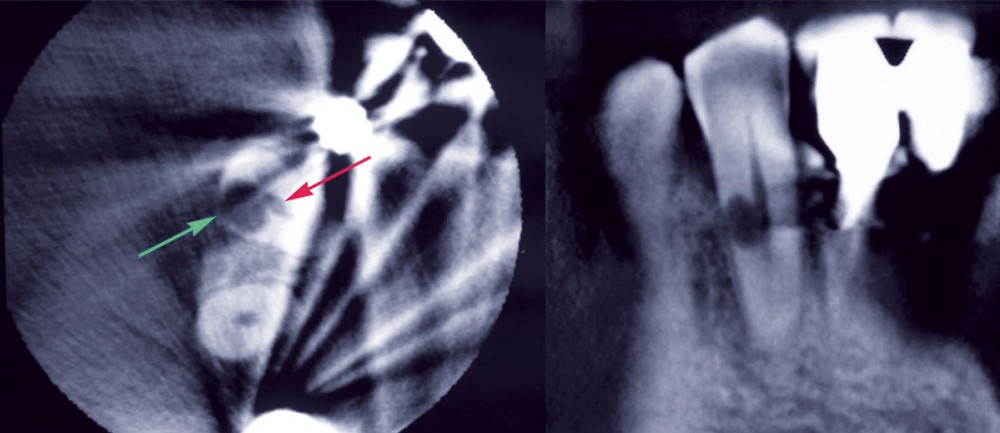

A l’image de l’ensemble des résorptions, un processus d’activation des cellules ostéoclastiques [2] est initié dans la région cervicale, entraînant une perte de substance dentaire (cément, dentine). Le facteur déclenchant reste la perte d’intégrité du cément qui ne permet plus une protection de la dentine contiguë. Cette brèche cémentaire occasionne une réparation où la balance ostéoblaste-ostéoclaste se voit déporter vers l’activité clastique. Cette balance est sous l’influence de plusieurs facteurs chimiques (hormones, cytokines, facteurs de croissance). La nature même de cette résorption n’est pas encore tranchée selon les auteurs qui la décrivent comme inflammatoire seule, inflammatoire initialement puis infectieuse voire infectieuse initialement puis inflammatoire [3].

Dans les cas de résorption cervicale invasive, il est difficile de mettre en évidence une étiologie, ce qui les classe dans les résorptions dites idiopathiques. Parmi 222 patients présentant 257 résorptions cervicales invasives, Heithersay [1] a cependant mis en évidence des facteurs prédisposants : l’orthodontie (avec force lourde), les traumatismes dentaires, le blanchiment interne (avec peroxyde d’hydrogène), les dommages directs à la jonction amélo-cémentaire lors de chirurgie.

Les caractéristiques principales de la résorption cervicale invasive sont :

– des parois dures au sondage à la base de la résorption. Cela permet un diagnostic différentiel avec les caries radiculaires qui apparaissent molles voire collantes au sondage. Un sondage appuyé entraînera un saignement par la stimulation du tissu inflammatoire de la résorption ;

– la présence fréquente d’un « pink spot » correspondant…